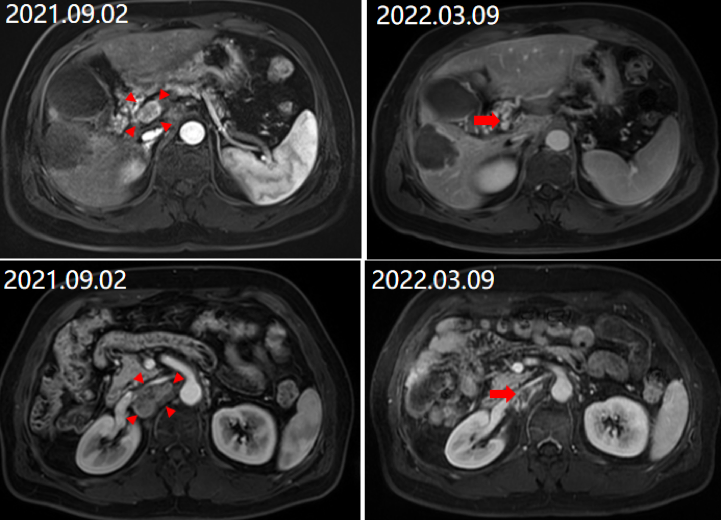

2021年9月2日复查MRI显示,肝门及腹膜后淋巴结增大,腹膜后一转移病灶局部增大,评效PD(图7)。

图片

图7.2021年9月2日复查MRI

2022年3月9日复查MRI,可见门脉后方肿大淋巴结、腹膜后肿大淋巴无活性且已接近消失,肝右叶肿瘤无明显活性,门脉右支癌栓消退再通(图8);总体评价为完全缓解(CR)。

图8.2022年3月9日复查MRI